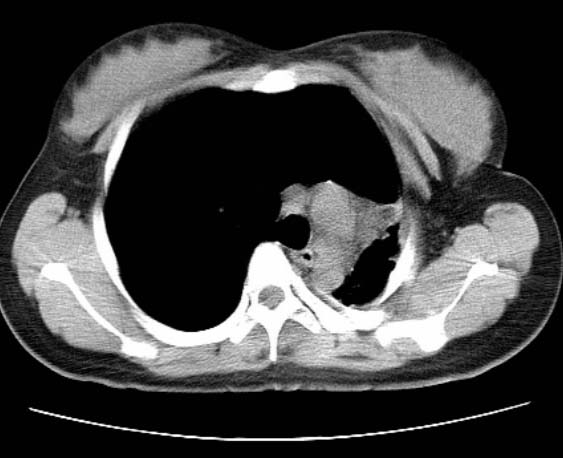

标题: CT25648:求教:是肺发育不全还是结核?

女  20岁。一月前咳血,诊“肺结核”抗痨治疗一月后,咳血停止,现复查。病人精神好。前后ct片对比未见明显变化。既往体检“正常”

1)考虑左肺结核并肺不张、支气管扩张。2)纵隔疝。

一侧肺发育不全

考虑左肺结核,左肺毁损,纵膈左偏,既往体检正常不可靠,tb一个月也不会这个样子的,有钙化,应该病程较长,冰冻三尺非一日之寒!

左肺发育不全。

考虑左肺结核,左肺毁损,纵膈左偏,既往体检正常不可靠,tb一个月也不会这个样子的,有钙化,应该病程较长,冰冻三尺非一日之寒